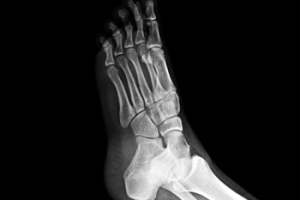

Common symptoms of stress fractures are pain and swelling near the weight bearing area on the injured bone. When initial x-rays are performed, it is possible that the fracture will not show up. However, once the stress on the area continues, the damage will increase, and the fracture will be severe enough to show up on an x-ray. Certain parts of the foot are more likely to develop stress fractures than others. Areas that typically have these fractures are: the metatarsals, the navicular bone, the calcaneus, tibia, and fibula.

Stress fractures in the feet are hairline cracks in the bone that often develop from repetitive force, rather than a single traumatic event. Stress fractures generally occur in the long bones of the foot, which endure significant impact during walking, running, and jumping. Overtraining, sudden increases in activity, or inadequate rest between workouts raise the risk. Foot structure also plays a role, with flat feet, high arches, or rigid arches contributing to uneven distribution of pressure that can stress certain bones. People with osteoporosis or low bone density are at higher risk, and nutritional deficiencies, such as inadequate calcium or vitamin D, may weaken bone strength. A podiatrist can confirm a diagnosis through examination and imaging, recommend appropriate footwear or orthotics, and advise whether surgery is required in severe cases. If you have symptoms of stress fractures in your feet, it is suggested that you make an appointment with a podiatrist for an exam, diagnosis, and treatment.